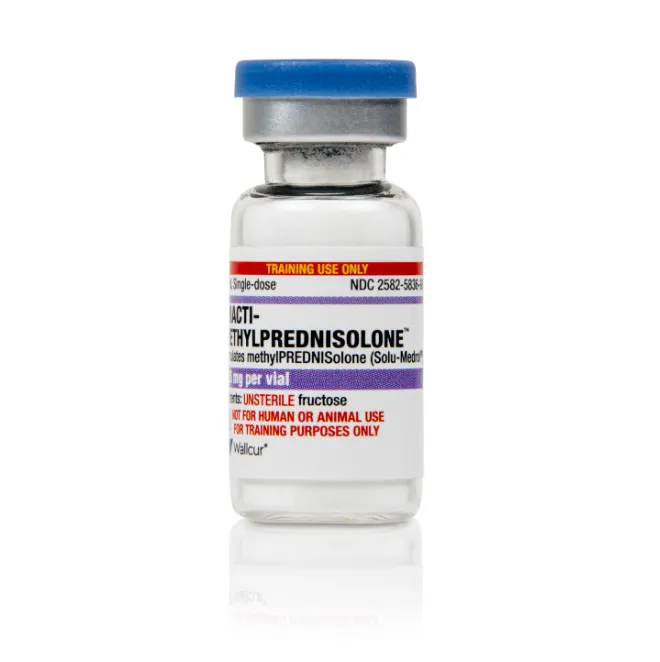

Intoxicação por citrato na contínua: quando suspeitar e como tratar

Intoxicação por citrato na contínua: quando suspeitar e como tratar